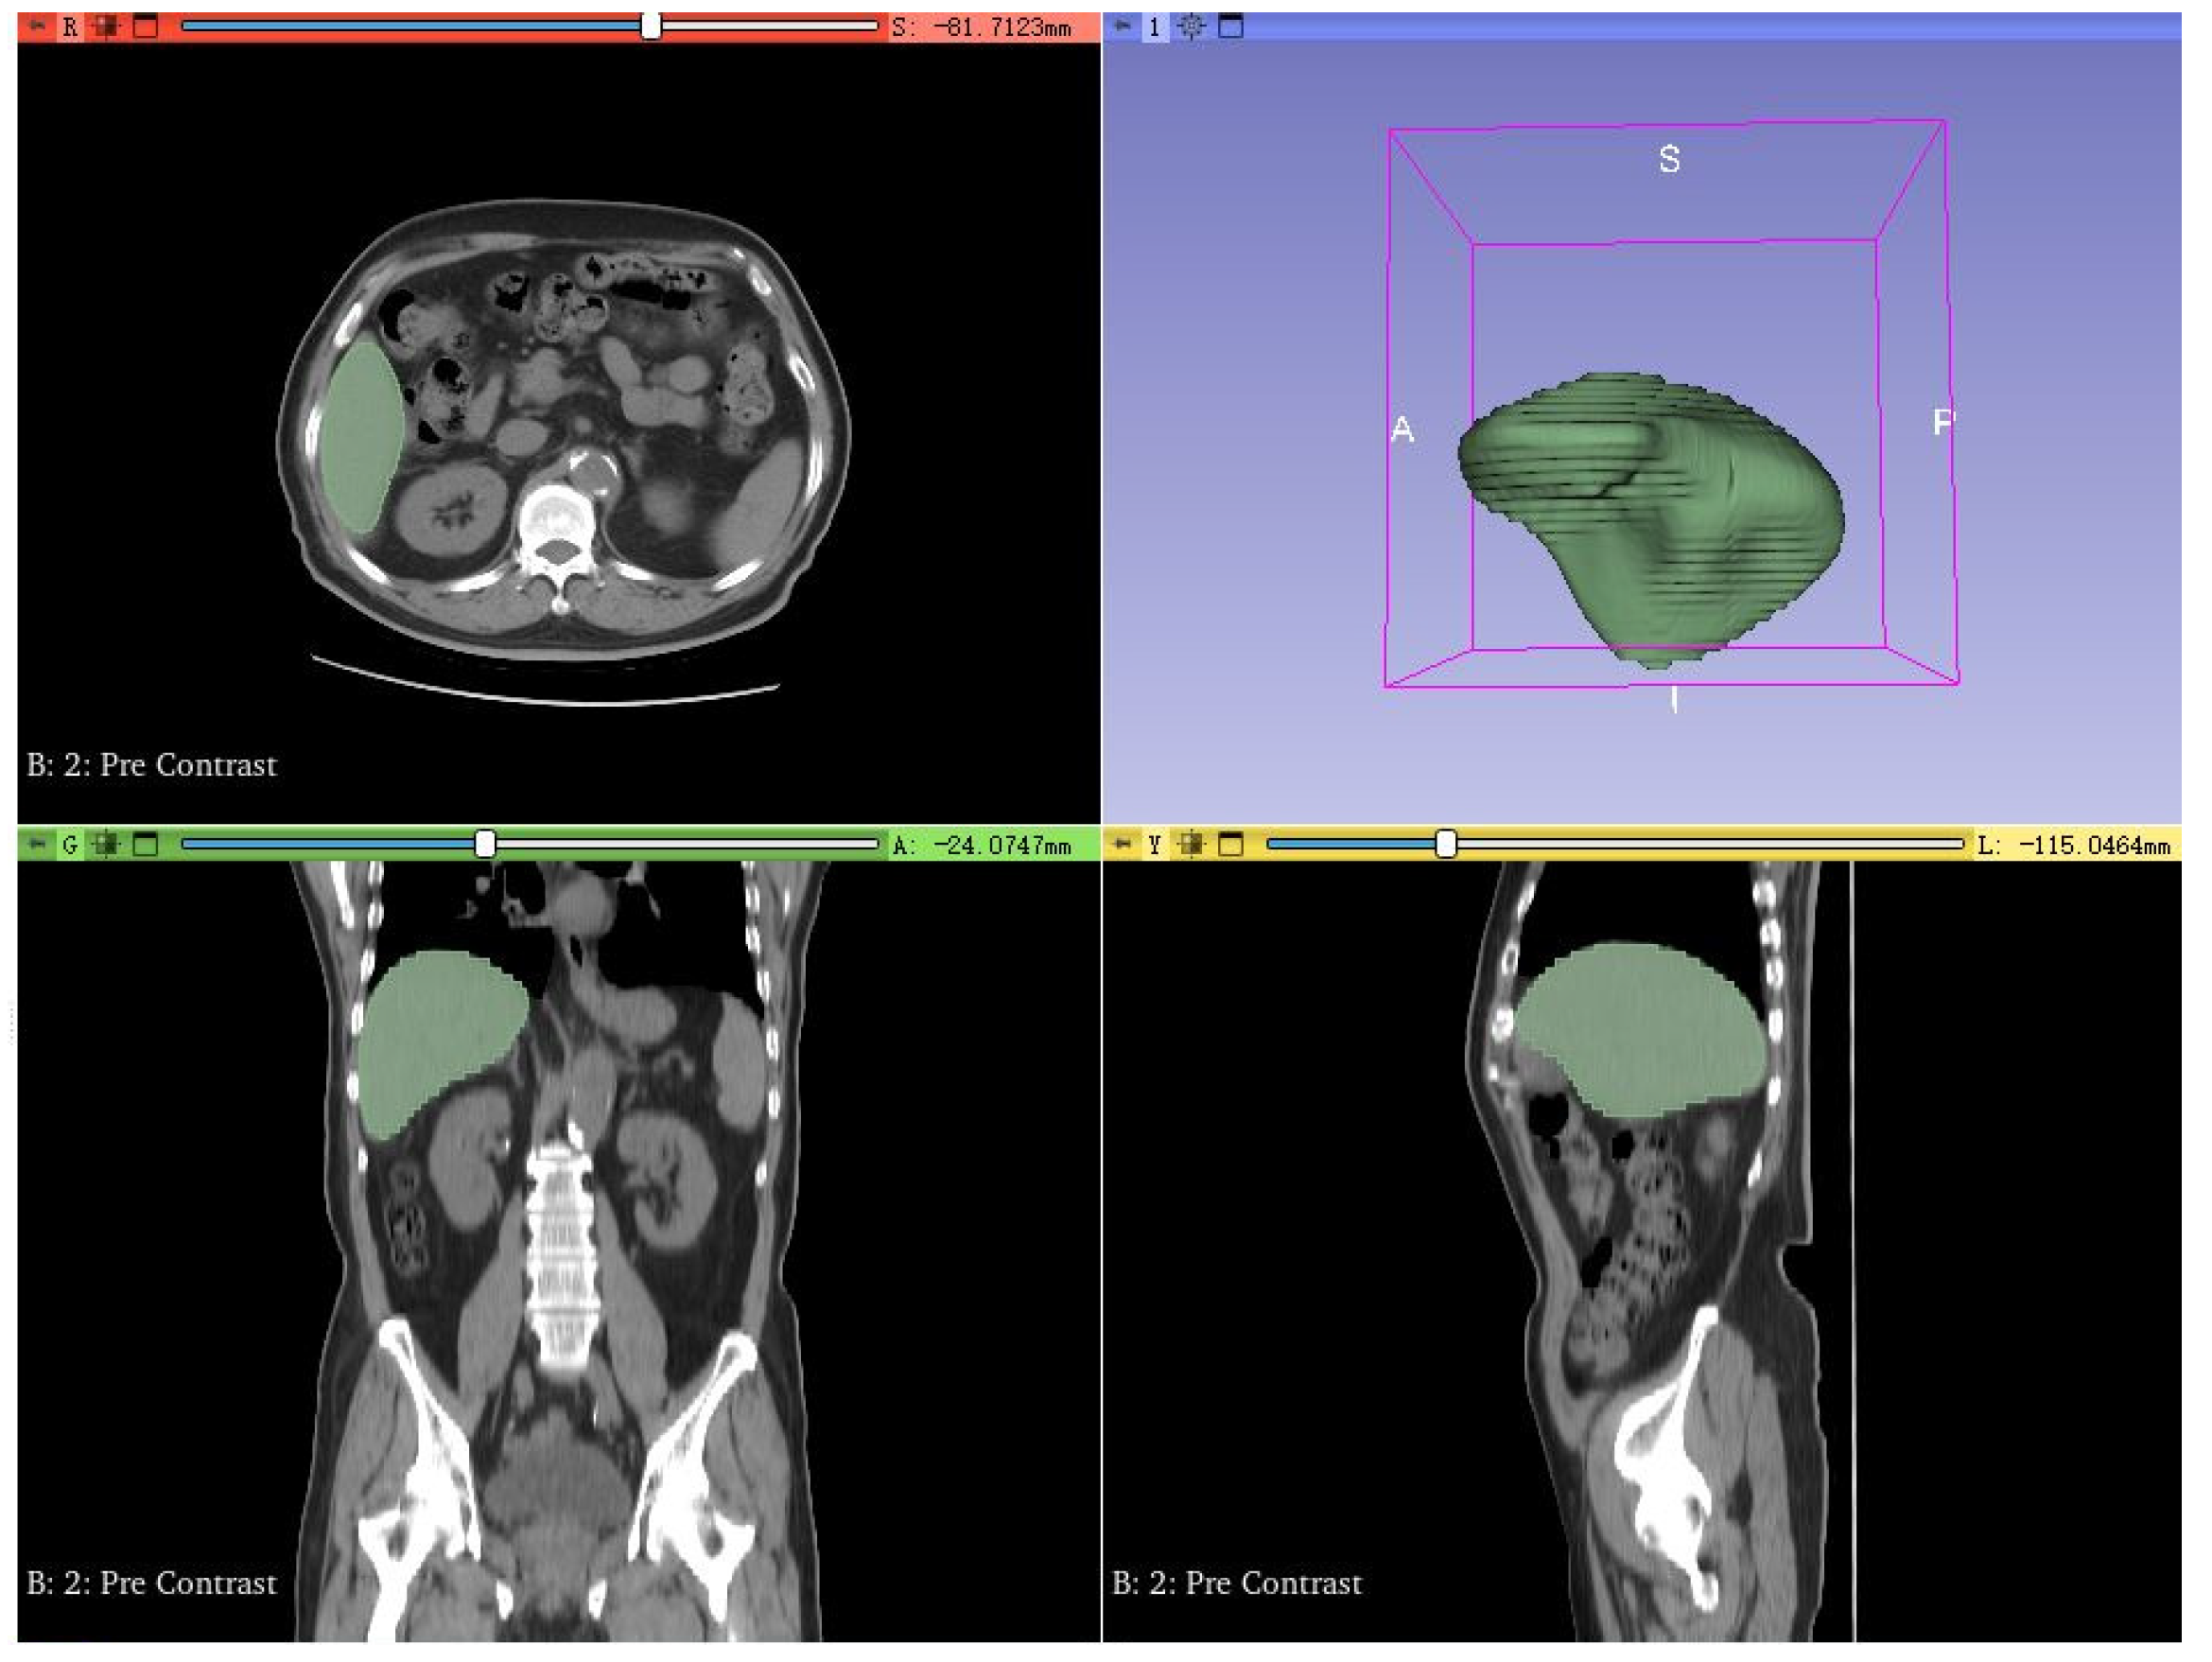

The clinical data in this study were obtained from enhanced CT scans of two patients with liver tumors at Beijing You’an Hospital, affiliated with Capital Medical University (Table 2). The study has been approved by the hospital’s ethics committee and informed consent has been obtained from the patients. All image data has been anonymized and complies with medical data protection regulations. The physicians first used version 5.4.0 of the 3D Slicer software [24] to complete CT image segmentation (Figure 1). Then they generated STL models of the liver and tumors through surface reconstruction algorithms for subsequent COMSOL simulation analysis.

Figure 1. Schematic diagram of segmentation results for clinical patient liver CT images.

Bioengineering 13 00421 g001